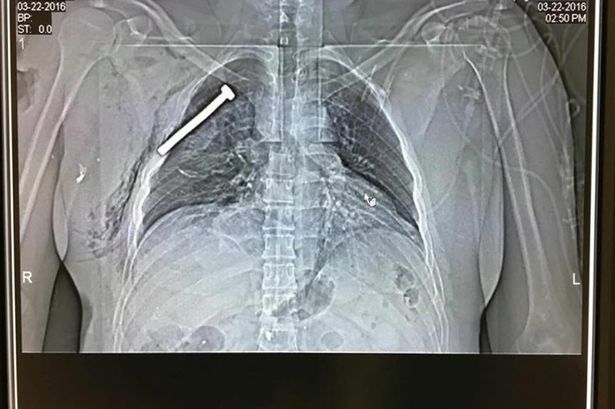

Σοκ προκαλεί η ακτινογραφία ενός από τους τραυματίες του μακελειού στις Βρυξέλλες στην οποία φαίνεται μία βίδα να έχει διαπεράσει το κορμί του.

Η ακτινογραφία του τραυματία, επιβεβαιώνει την αποκάλυψη των αρχών ασφαλείας, ότι οι τρομοκράτες είχαν βάλει καρφιά και βίδες στις βόμβες, προκειμένου να σκοτώσουν περισσότερους ανθρώπους.

Τη φωτογραφία της ακτινογραφίας δημοσίευσε το πρακτορείο ΕPA.